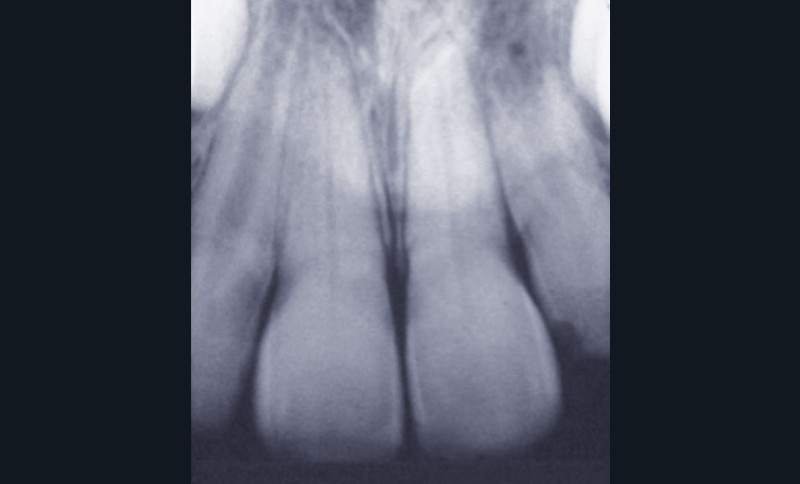

La pulpe de la première molaire permanente dans tous ses états (fig. 1 à 3)

L’immaturité tissulaire de la première molaire permanente lui confère des propriétés biologiques particulières : l’édification radiculaire et la fermeture des apex peuvent durer de 1 à 4 ans après l’éruption de la dent, période au cours de laquelle la dentine est plus perméable. Pendant cette période, la pulpe conserve un potentiel de cicatrisation très élevé. Ainsi, les thérapeutiques doivent être adaptées : la carie sera évaluée selon la classification ICDAS 2 (www.icdas.org) et le potentiel de réparation pulpaire sera exploité au maximum afin de conserver la vitalité le plus longtemps possible. Cependant, l’état histologique pulpaire n’est pas corrélé à la situation clinique, et le choix thérapeutique face à une carie profonde reste problématique : c’est pourquoi un gradient thérapeutique sera appliqué. En fonction de la sévérité de l’atteinte, on pourra pratiquer une excavation en deux temps (« stepwise »), un coiffage direct ou une pulpotomie.